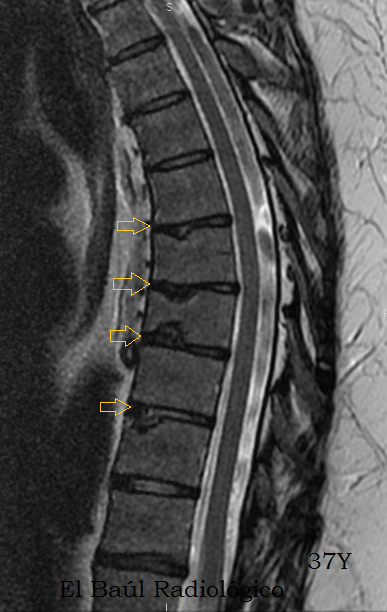

Hombre de 37 años. Dorsalgias desde la juventud.

FIGURA 7-A) FSE-T2. Irregularidad  de los platillos vertebrales dorsales, degeneración de los discos y moderado acuñamiento de los cuerpos vertebrales. (Flechas amarillas). E de Scheuerman. Acentuación de la cifosis dorsal.

FIGURA 7-B) FRFSE-T2. Irregularidad  de los platillos vertebrales dorsales, por herniaciones intraesponjosas, degeneración de los discos y moderado acuñamiento de los cuerpos vertebrales. (Flechas amarillas). E de Scheuerman. Acentuación de la cifosis dorsal.